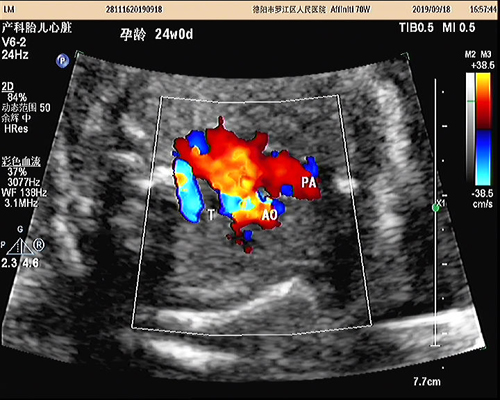

我院引進四維彩超 準媽媽可就近“拍照”

? ? ? ?9月1日,我院引進胎兒四維超聲檢查與胎兒心臟超聲篩查新技術,填補了羅江區(qū)該項超聲技術空白。

? ? ? 截止9月19日,我院特檢科已為33名孕婦做此兩項檢查。這兩項技術的順利開展進一步提高了我院胎兒產前檢查的準確性,將有助于減少嚴重畸形、致死性畸形的發(fā)生率。